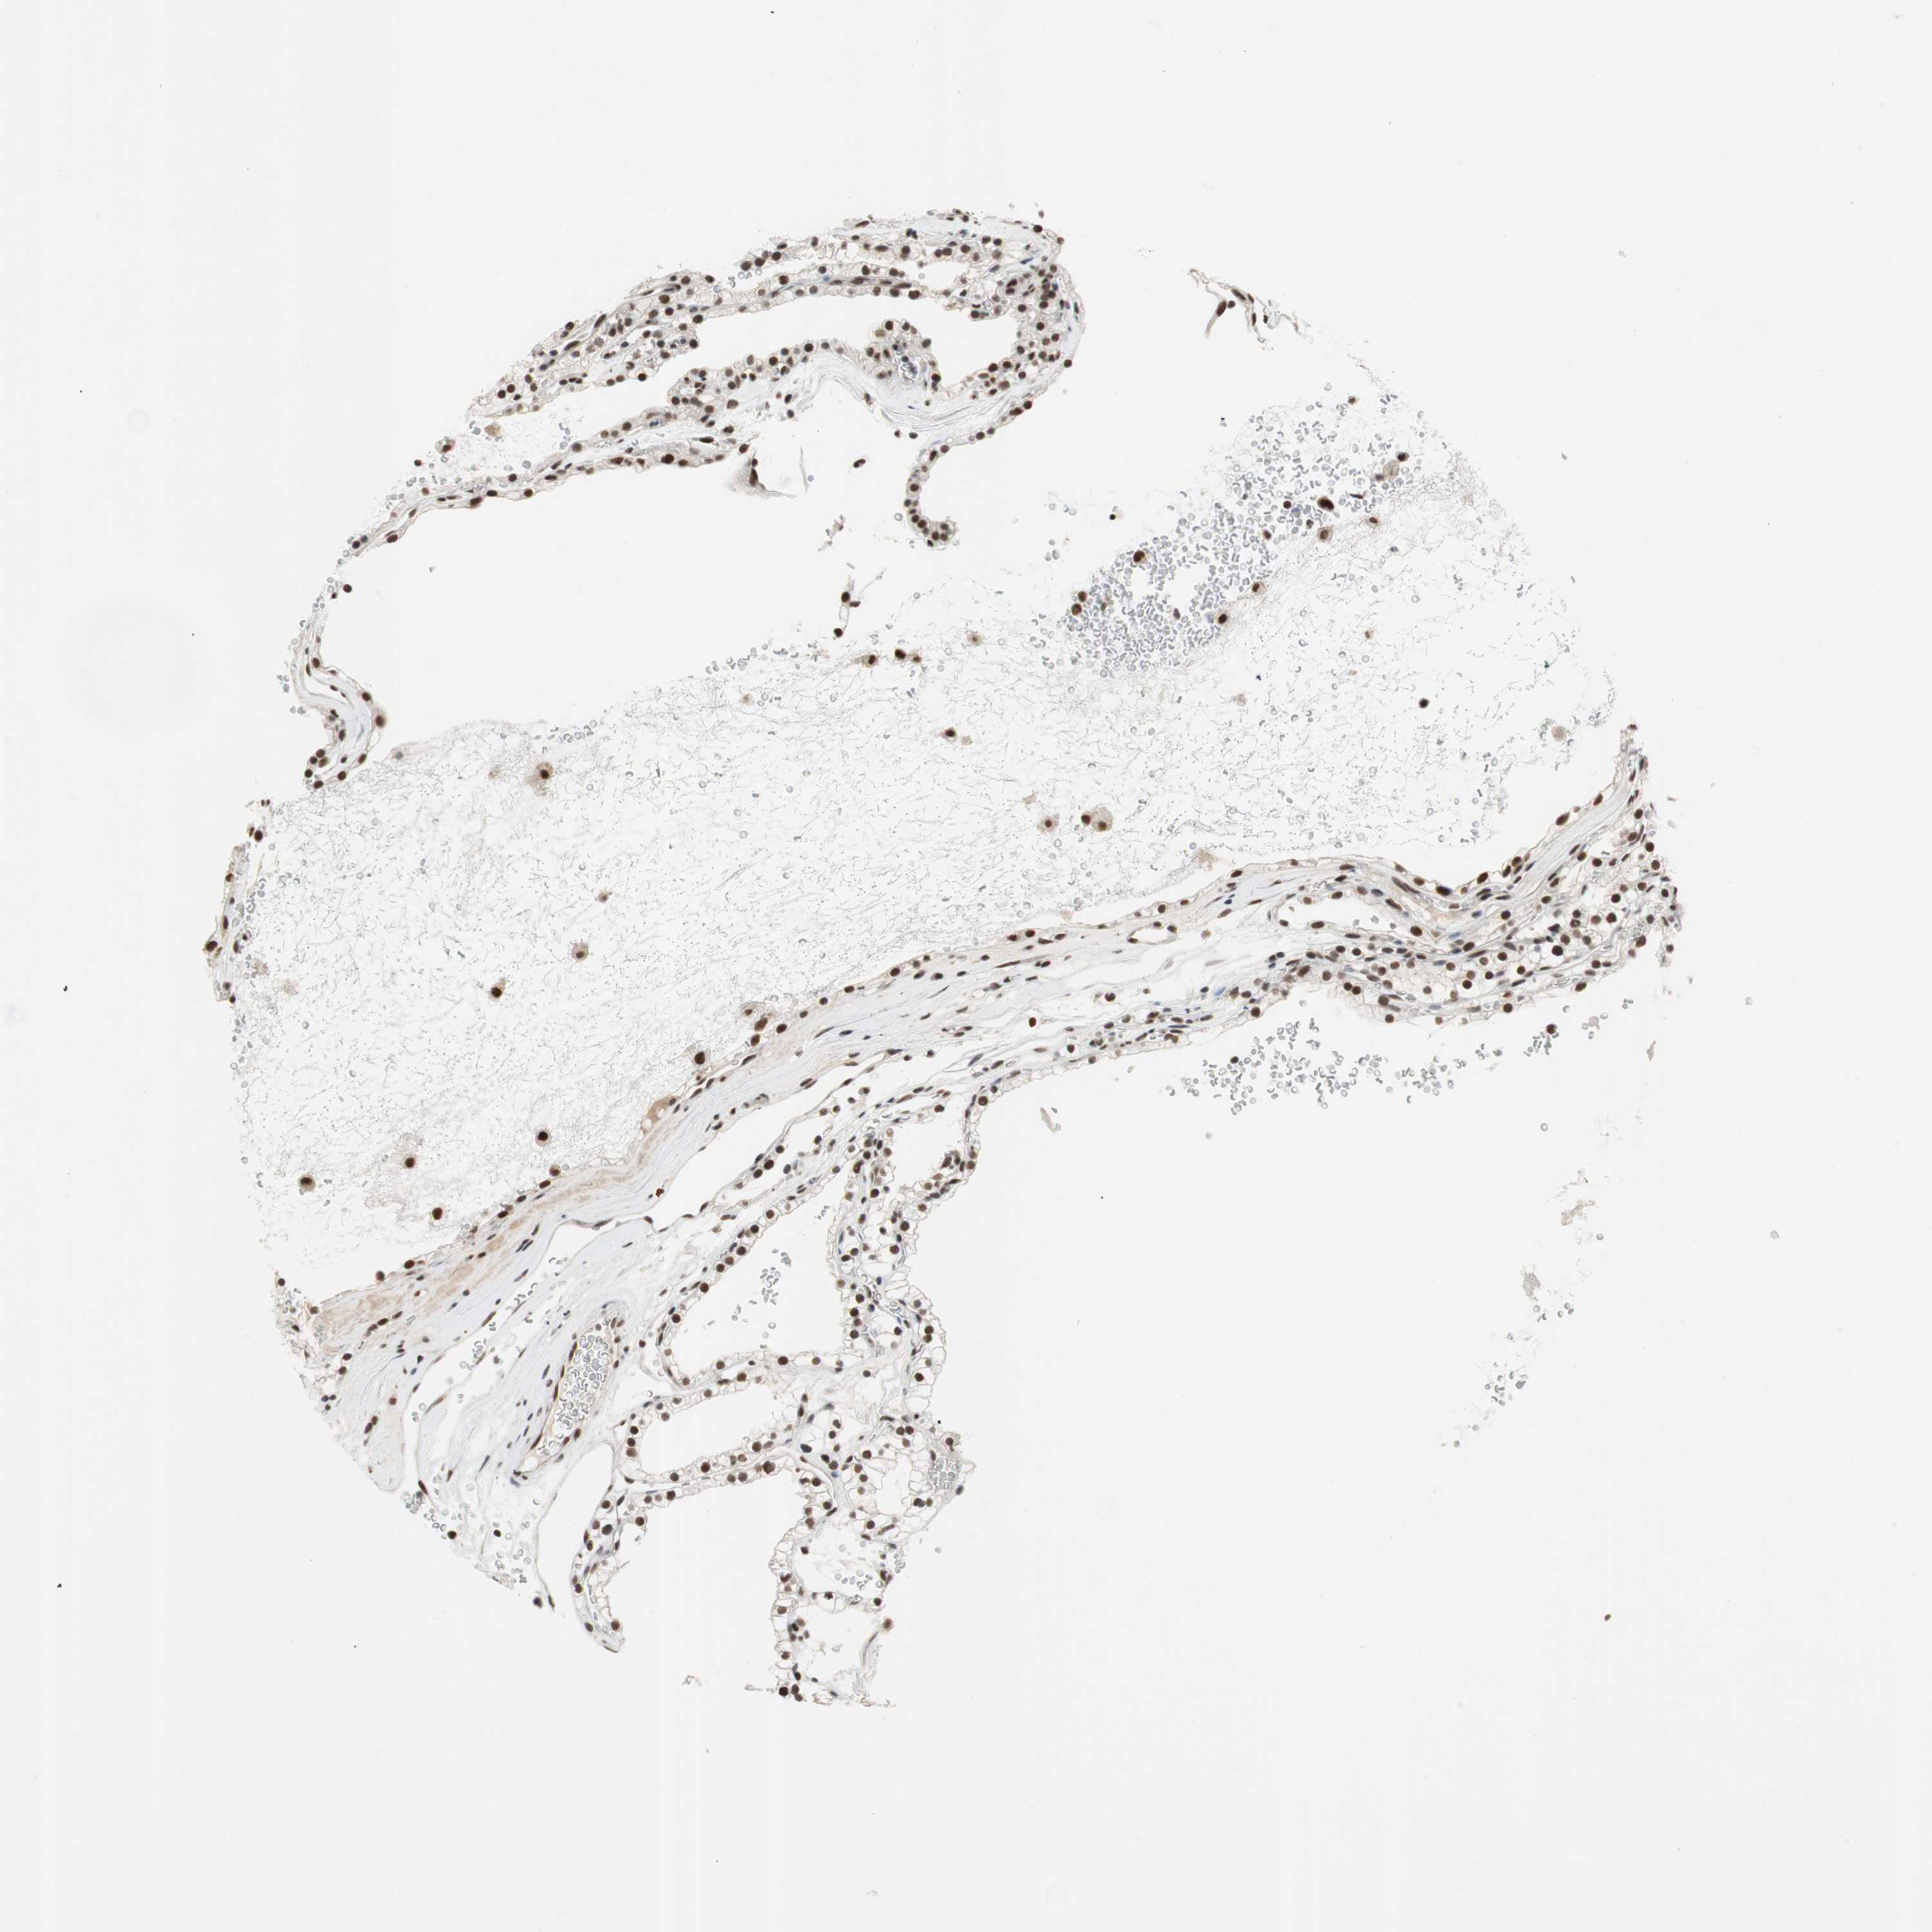

Renal cancer

Kidney renal clear cell carcinoma